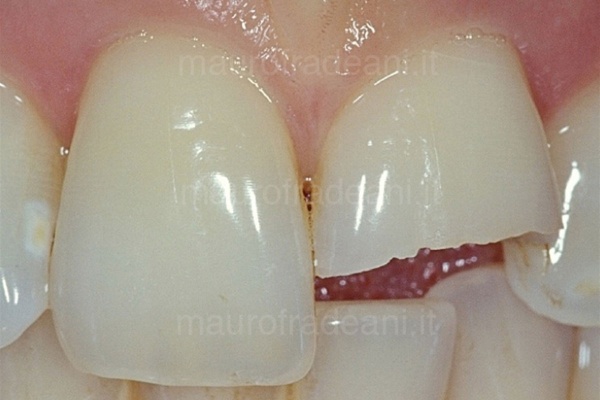

I principali trattamenti quali otturazioni e ricostruzioni, volti a preservare il più possibile la sostanza dentale ripristinando l’integrità dei denti, si effettuano con materiali ad alta valenza estetica: resine composite o ceramica che garantiscono un risultato eccellente e stabile nel tempo.

L’impiego di tecniche di previsualizzazione del risultato finale quali il mock-up, oltre a facilitare al paziente la comprensione del piano di terapie proposto, gli permette addirittura di testare per qualche ora o per qualche giorno il nuovo sorriso. Preparazioni dentali minimali permettono la massima preservazione di struttura dentale e, in gran parte dei casi, evitano il ricorso alla somministrazione di anestesia.

Richiedono una preparazione dentale talmente minimale da non dover ricorrere, nella maggioranza dei casi trattati, alla somministrazione dell’anestesia.